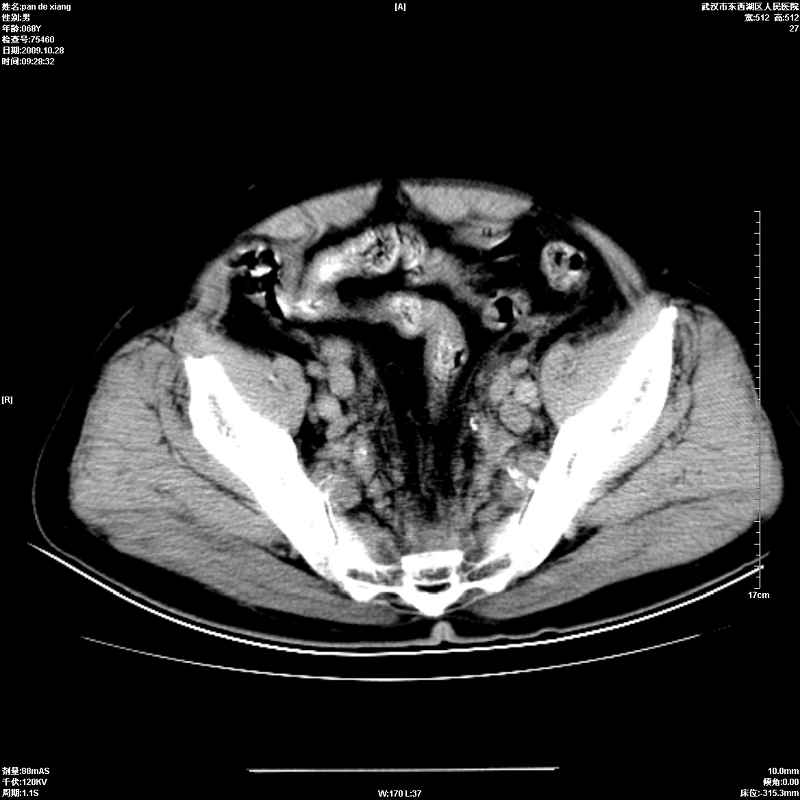

以下是引用杀毒软件在2009-10-28 20:41:00的发言:[br]结合临床考虑---白血病双肾改变或淋巴瘤。

以下是引用zxl51642在2009-10-29 9:59:00的发言:[br]结合临床“单克隆免疫球蛋白血症”,考虑双肾为继发损害并肾功能不全(尿中大量igg及少量iga、igm等大分子免疫球蛋白滤出所致继发损害),椎前软组织肿块为髓外造血。与浆细胞瘤有区别,平扫时有战友说的很清楚。